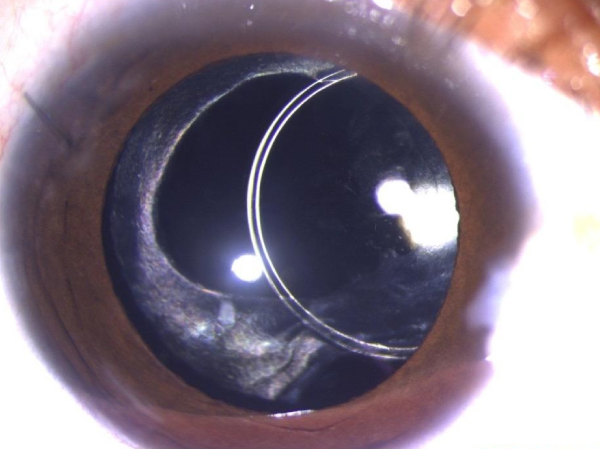

Sunset Syndrome

Sunset syndrome intraocular lens displacement before surgery

Pre-Operative

Sunset syndrome corrected after eye surgery Kerala

Post-Operative